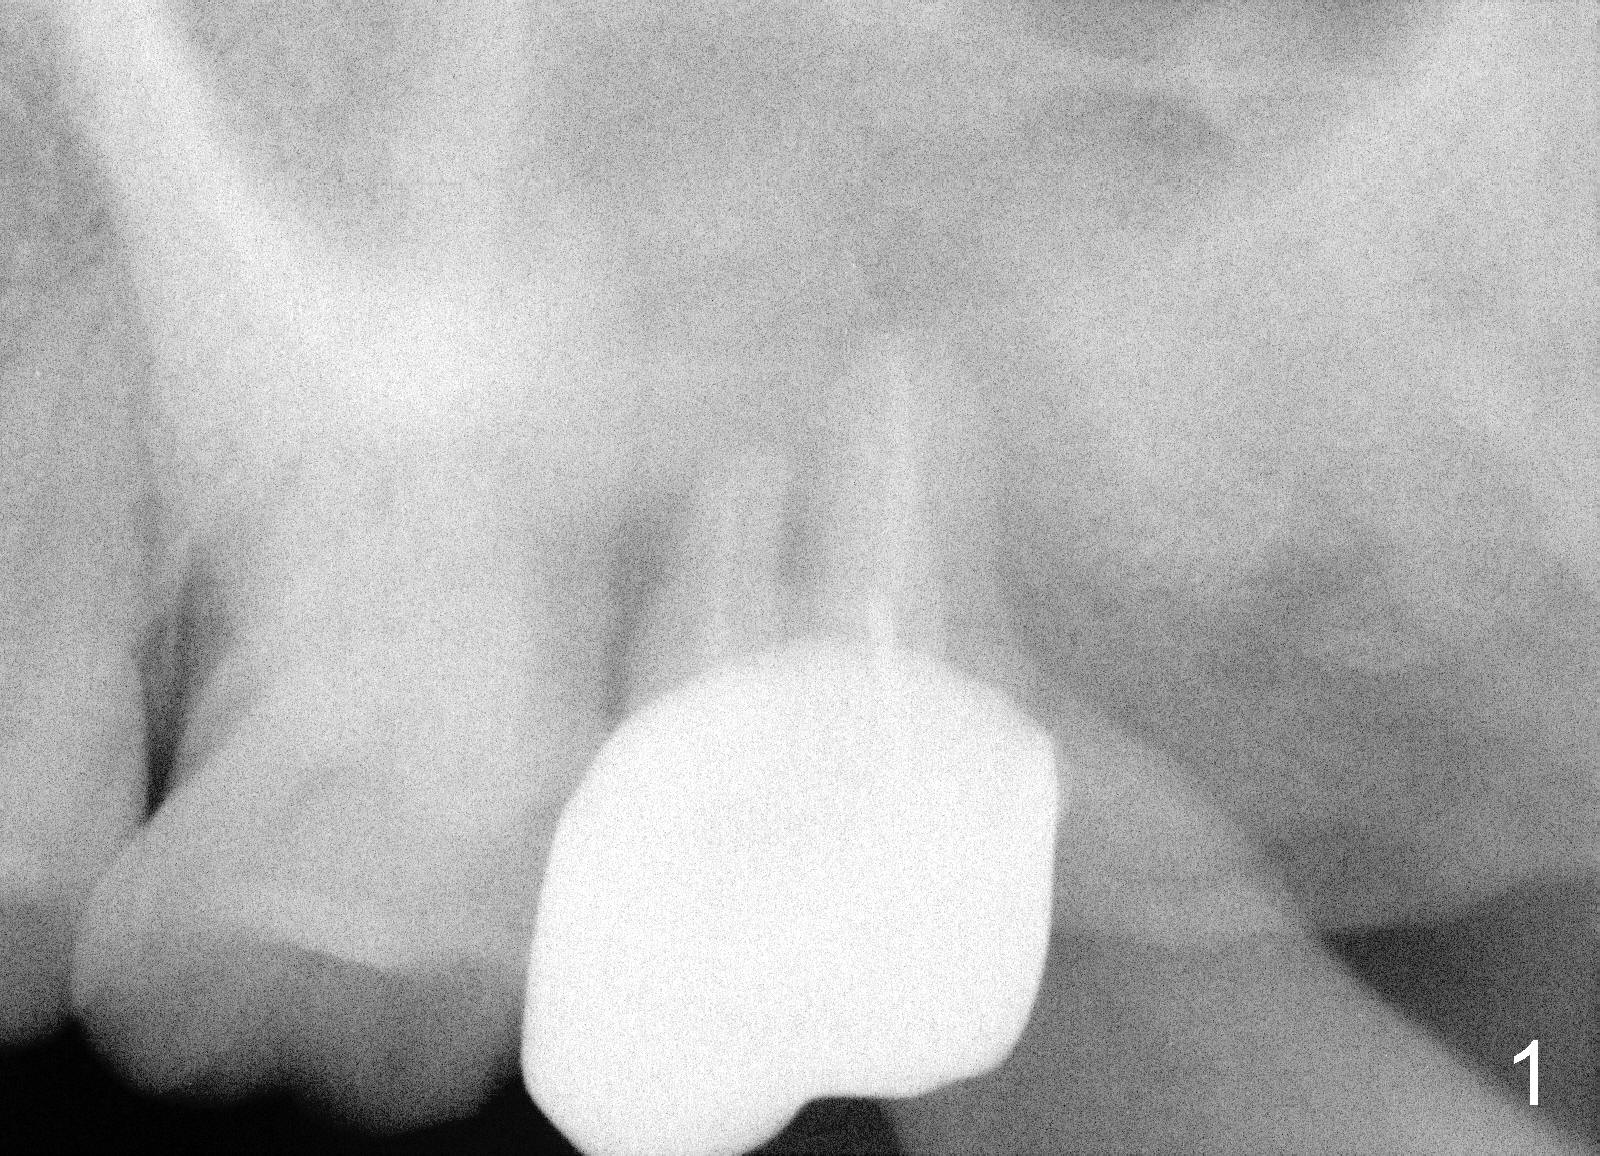

A 50-year-old lady presented to clinic with chief complaint of a loose tooth upper left.  The tooth #15 has complex endo-perio disease (Fig.1,2).  It was extracted on November 29, 2012.  She returned to clinic for implant placement on January 28, 2013.  Under local anesthesia, osteotomy was prepared with combination of bone expansion and drilling (Fig.3: 4x14 tapered drill).  She was not comfortable with tapping.  Finally, Tatum tapered implant (6x14) was placed (Fig.4) with 35 Ncm.  She felt dizzy when she stood up from dental chair. She felt better by the evening of January 29, 2013.  But the following morning, she did not feel good.  She wonders when the symptom will disappears.